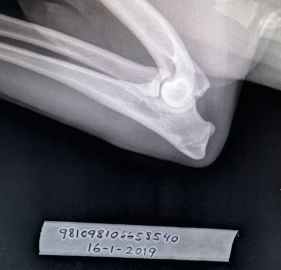

HD : A/A

AD : 0/0